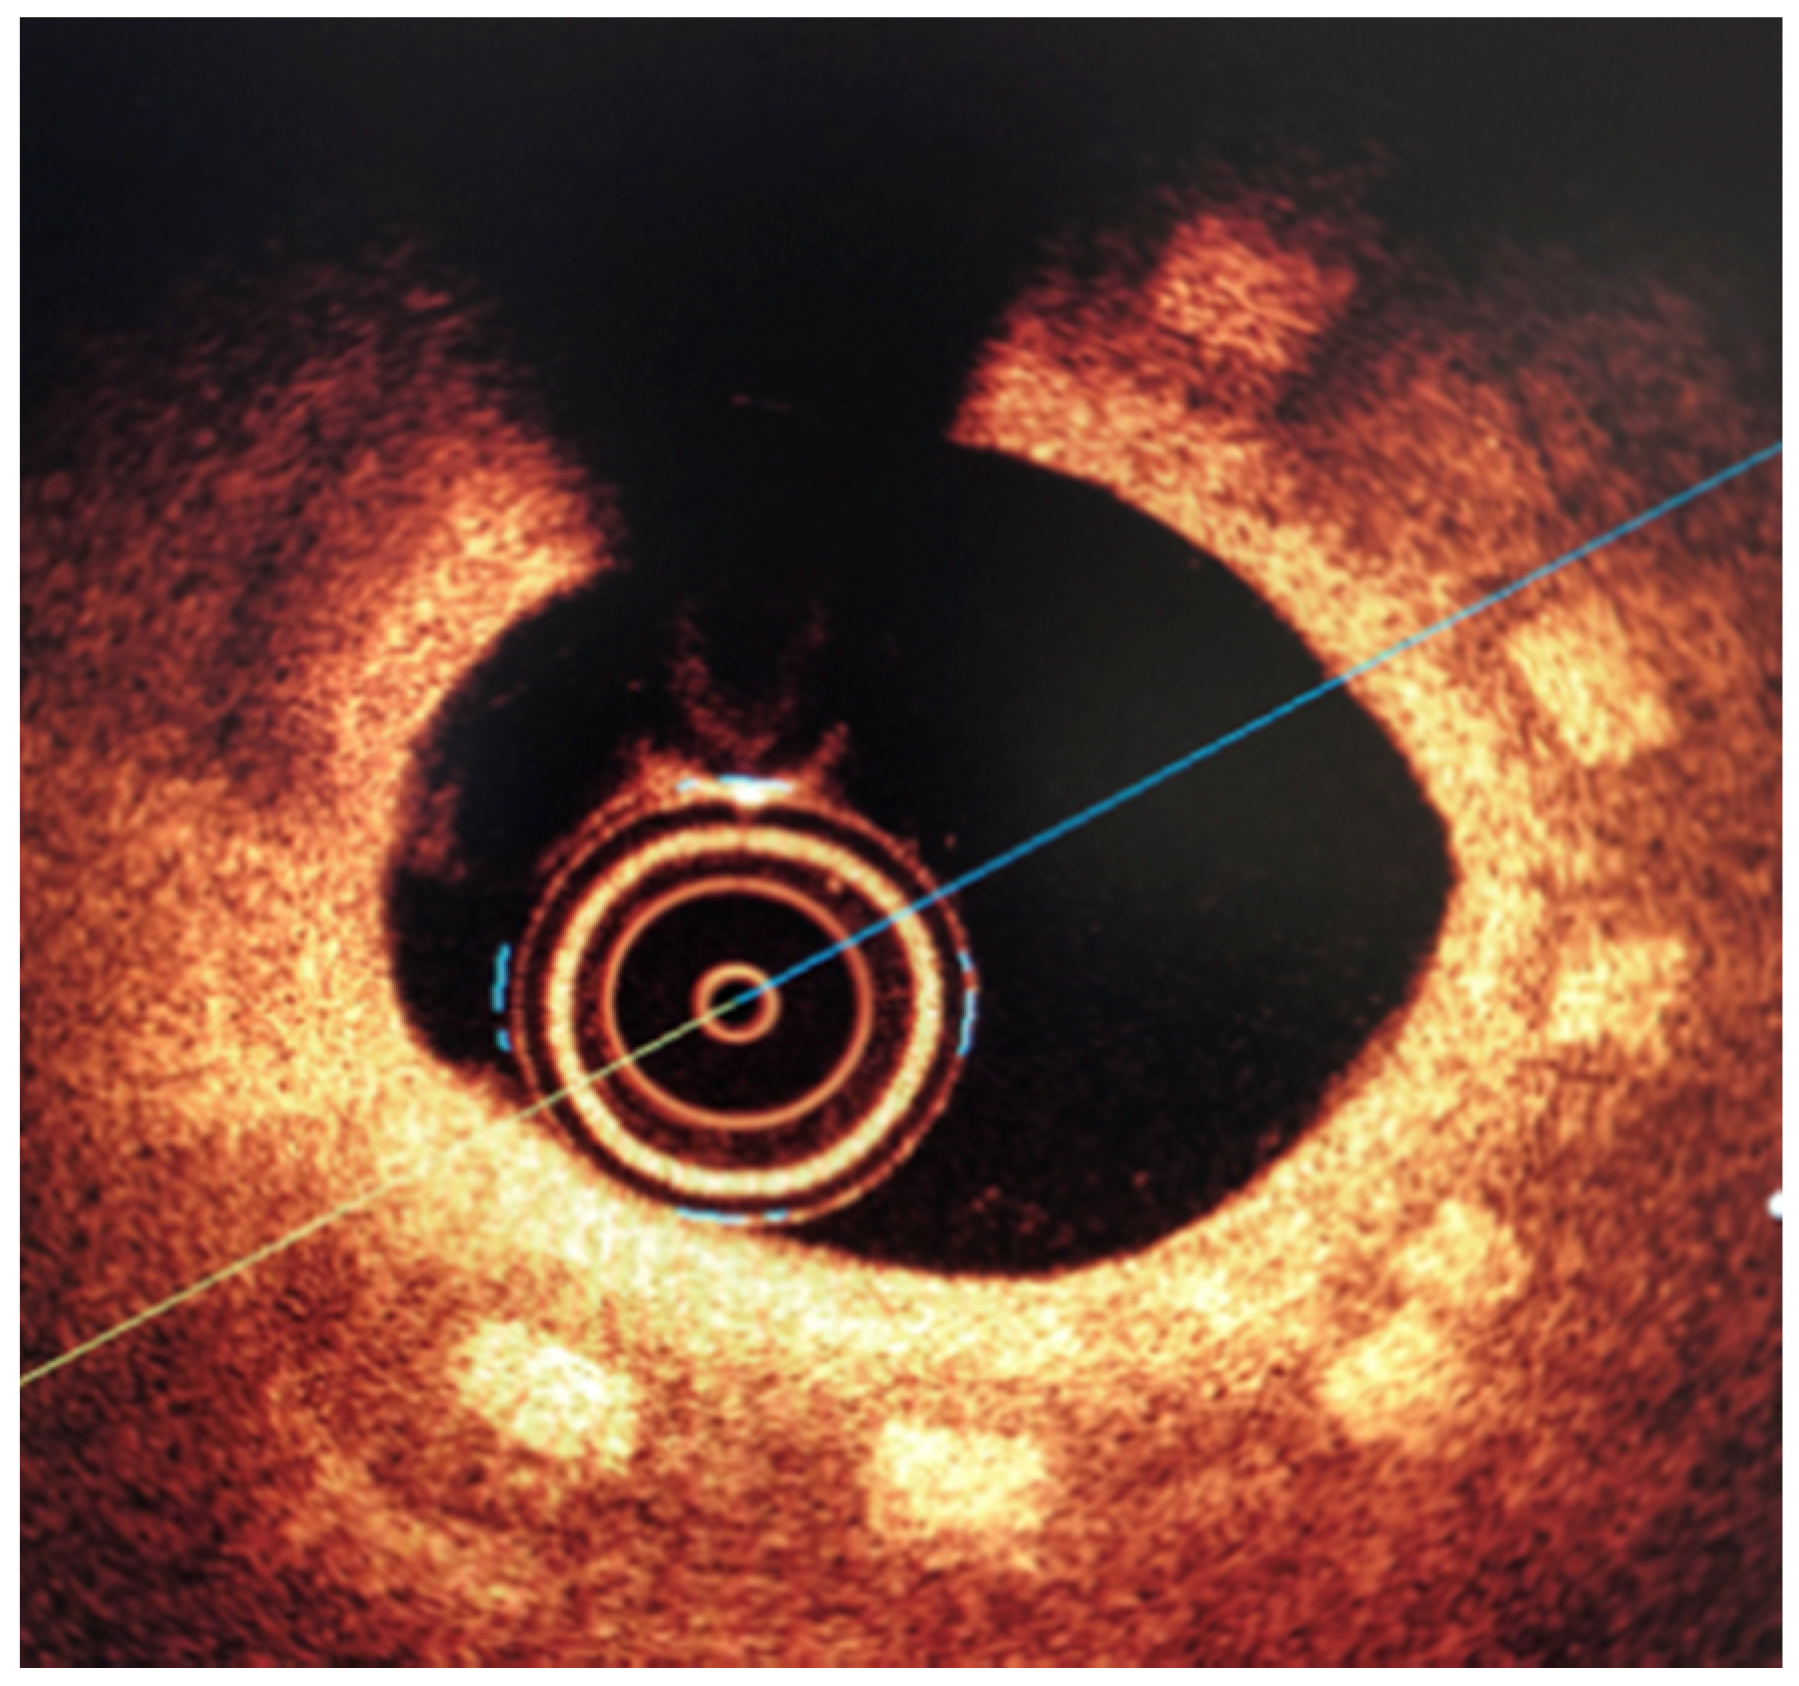

2.4. Biological Reponse in the Large Model of Coronary In-Stent Restenosis

The part of study was approved by local bioethical committee for animal experimentation (Medical University of Silesia, Katowice, Poland). To validate the mathematical and mechanical modeling tests described above, three PLGA/PLLA blend polymer stents (3.0 in diameter, 15.0 mm length) were implanted with standard percutaneous techniques in three coronary arteries of domestic swine with 110% overstretch. Following coronary angiography, intravascular optical coherence tomography (OCT) was utilized before and after the stent implantation to size the vessel. Stents were deployed after reaching body temperature with slow in mid portion of one of the three coronary arteries with stepwise inflation—2 atmospheres per 5 s. Following post implantation coronary angiography and OCT were performed. Animals were scheduled for 28-day follow-up with coronary angiography and OCT.

3.2. Biological Response

All three stents were implanted successfully. In coronary angiography stents showed enough radial force to support overstretched vessel (Figure 13). The OCT has shown good stent apposition and the analysis has shown lumen enlargement post implantation 24% as shown in Figure 13c. At 28-day follow-up, all stents were covered with neointima, and struts embedded. Interestingly the signs of material hydrolysis were observed thus proving the polymer amorphic properties (Figure 14).

Figure 13.

Acute outcome after PLGA/PLLA blend polymer stent implantation in coronary angiography (a) and optical coherence tomography (b). Lumen area increase before and after implantation (c). Geometrical view of vessel after stent implantation (d).

Figure 14.

Optical coherence tomography at 28 days follow-up show optimal vascular response and stent geometry. Stent struts show blurred image, a sign of early hydrolysis (rectangle).

The results presented in the mathematical modeling has shown sufficient radial force, inflate, expand and implant a tested stents in the coronary vessel. This was validated by mechanical radial force tests as well as implantation in the in-vivo, porcine in-stent restenosis model. The implanted stents provided sufficient strength to withheld the compression of on oversized vessel. The struts were well apposed. At long-term follow-up the stent areas remained similar, thus confirming time-dependent tensile and radial strength. This pivotal study showed optimal neointimal coverage of all stents struts which were embedded without excess of neointima. Additionally, the struts in OCT were absorbable to light from OCT, in contrary to immediate effect after implantation. This could be the result of hydrolysis, and amorphous character of the tested polymer. This requires however further investigation of the explanted material.